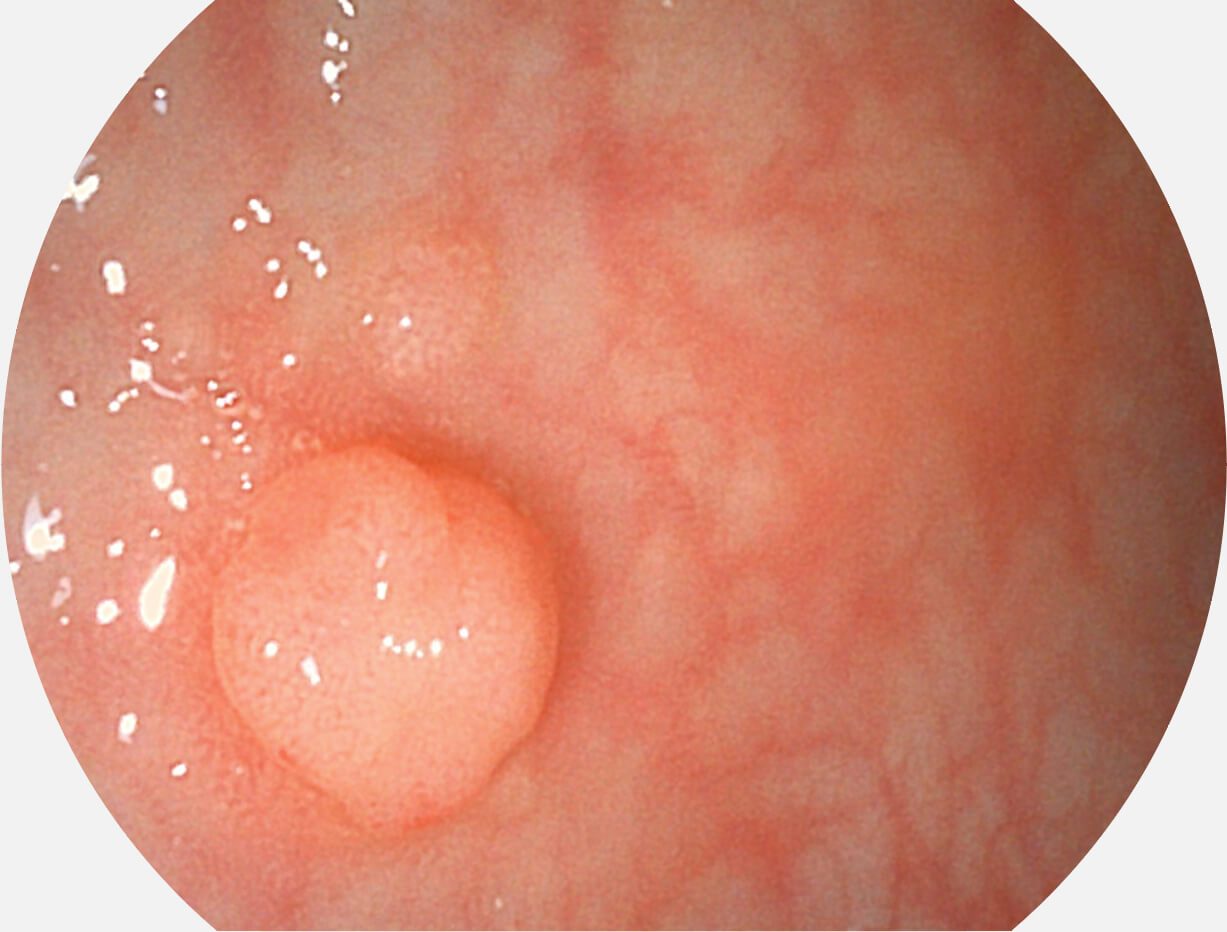

采用无损耗高清数字接口,视频输出分辨率≥1920×1080,图像清晰、细腻。

采用光路合束技术,光谱自由度高,实现了更丰富的照明模式,染色模式SFI及VIST,从远景到近景,助力消化道早期疾病诊断。